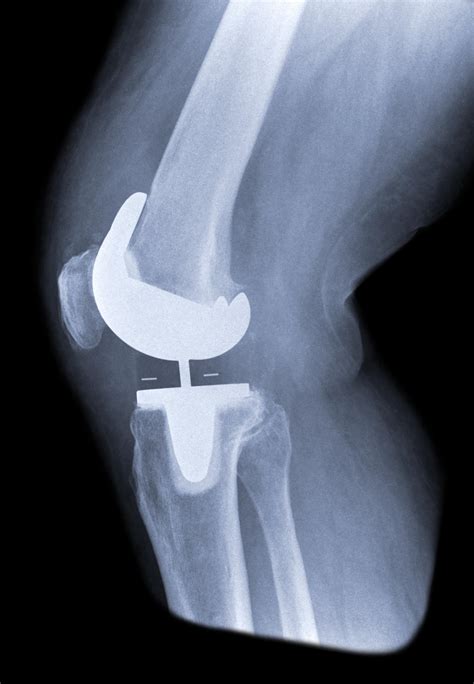

Deciding to undergo orthopedic surgery is a significant milestone for anyone suffering from chronic joint pain. As you begin your journey toward recovery, you may find yourself searching for Knee Replacement Images to better understand the procedure, the anatomy involved, and what to expect during the healing process. Visualizing the surgery and the internal components—such as metal implants and high-grade plastic spacers—can demystify the experience and help you feel more confident in your decision to improve your mobility and quality of life.

Total knee arthroplasty, or knee replacement, is a highly successful surgery designed to relieve pain and restore function in diseased or damaged knee joints. By looking at Knee Replacement Images, patients can see how an orthopedic surgeon removes the damaged cartilage and bone from the surface of the knee joint and replaces them with artificial components. These components are meticulously crafted to mimic the natural movement of a healthy knee.

The surgery generally involves three primary parts:

• The Femoral Component: A metal piece that attaches to the end of the thigh bone (femur).

• The Tibial Component: A metal tray that sits on top of the shin bone (tibia).

• The Patellar Button: A plastic piece that replaces the surface of the kneecap.